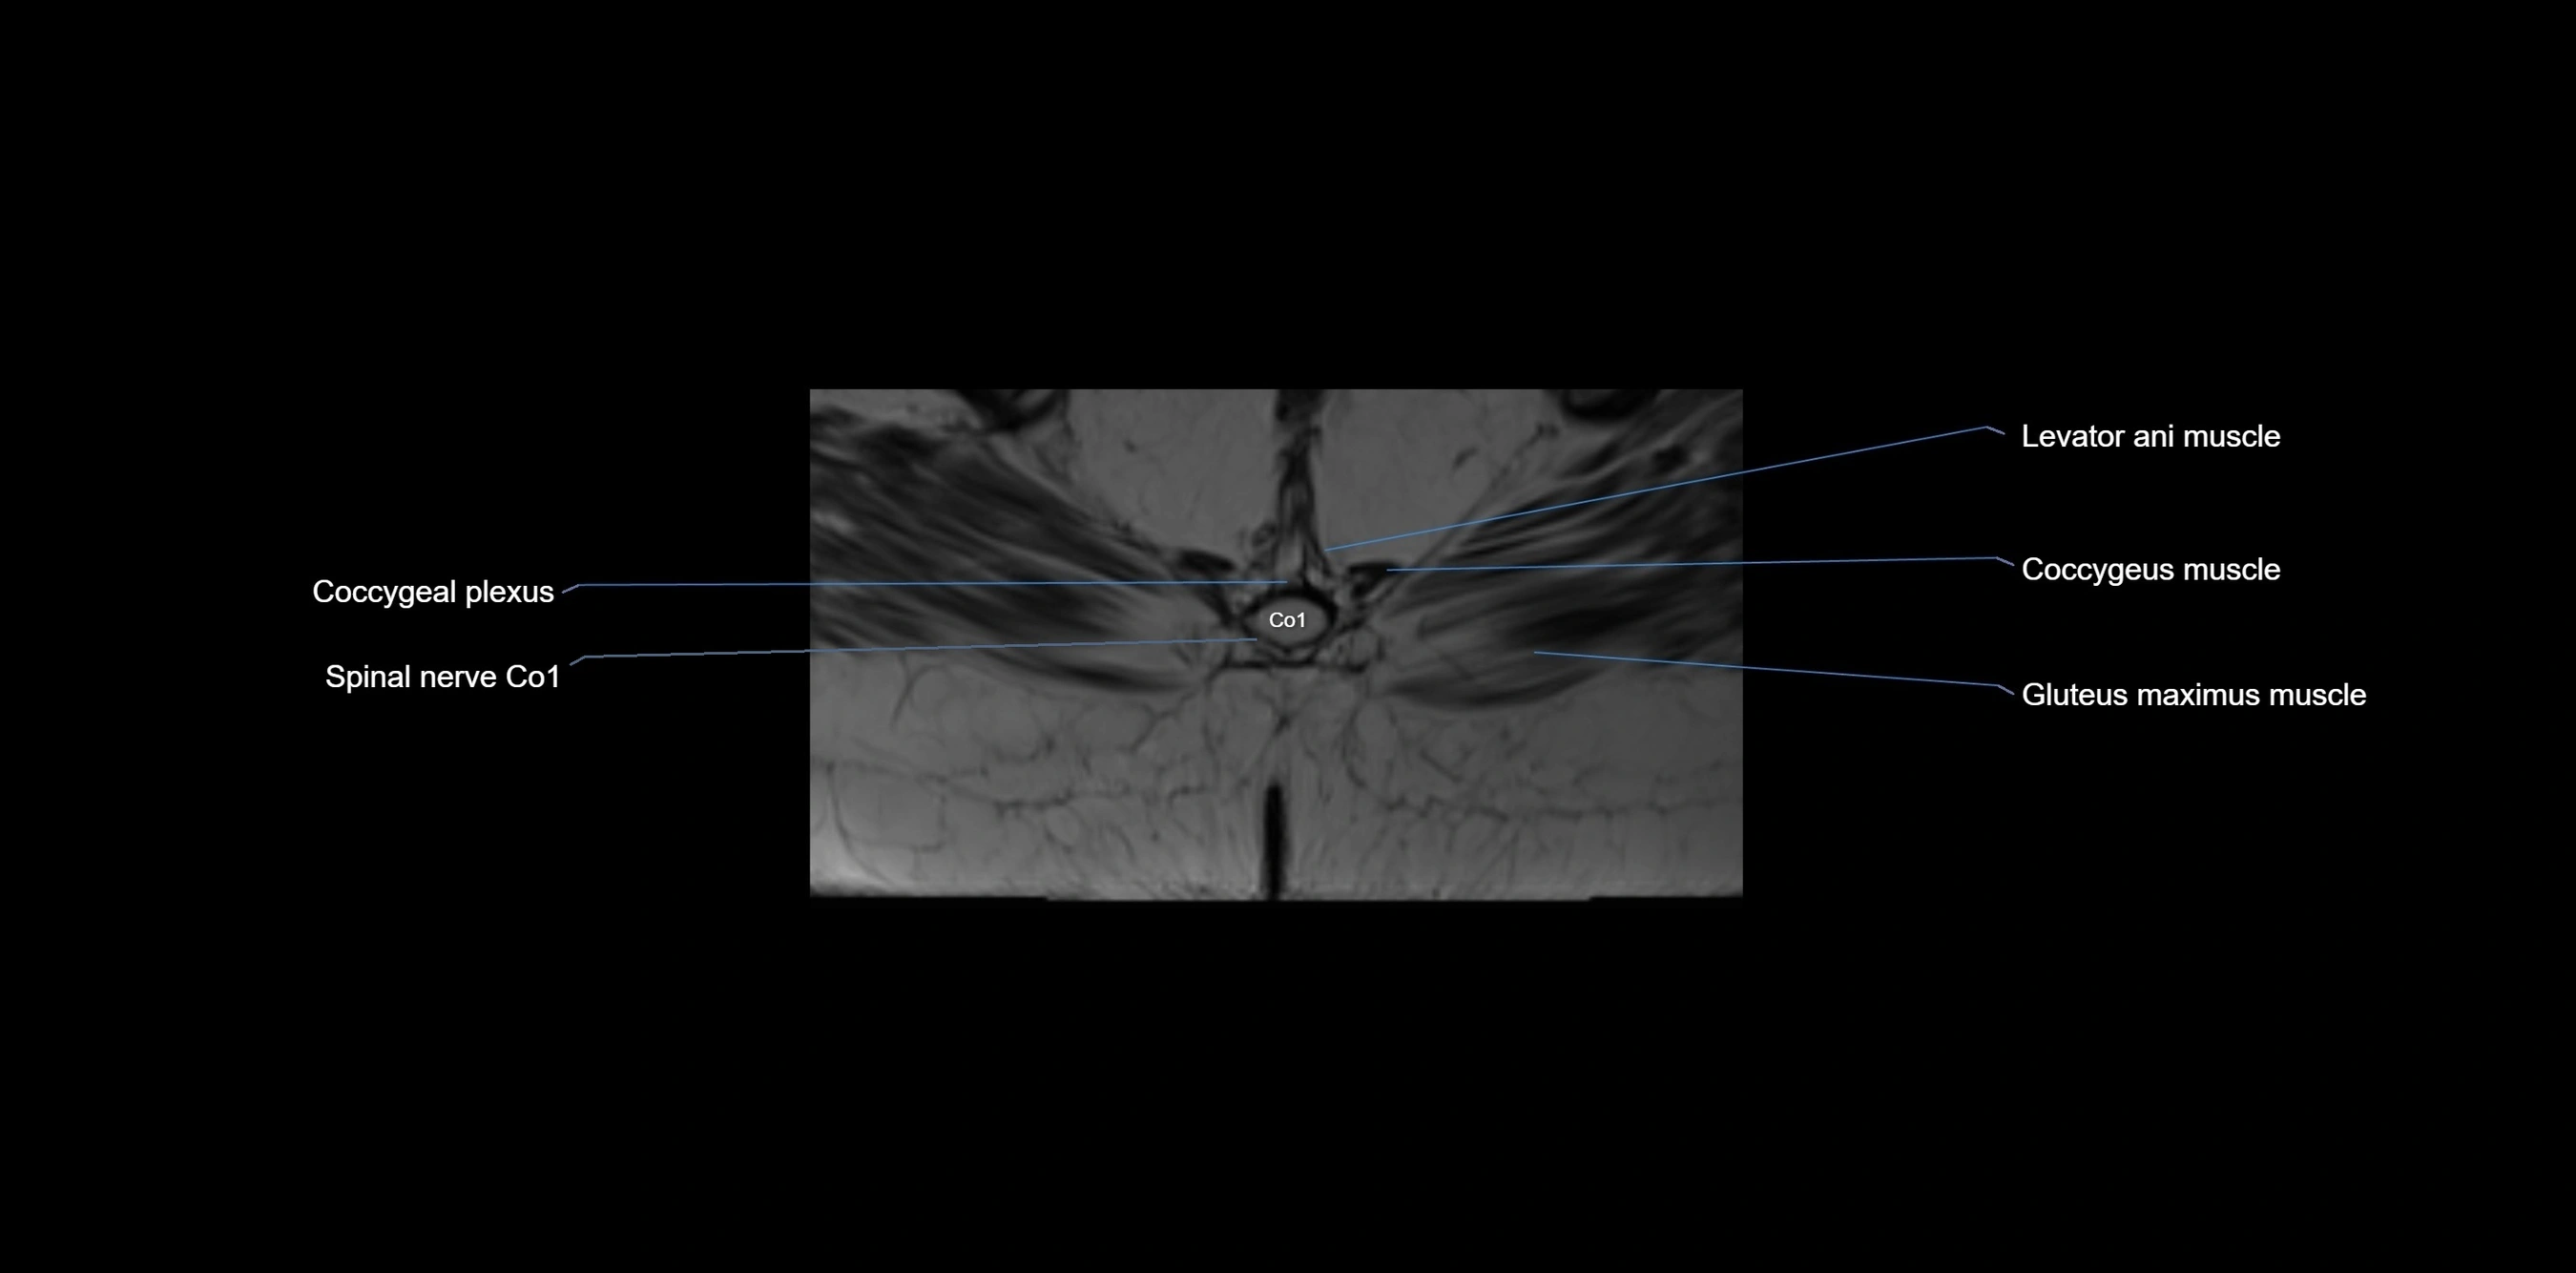

MRI image

image